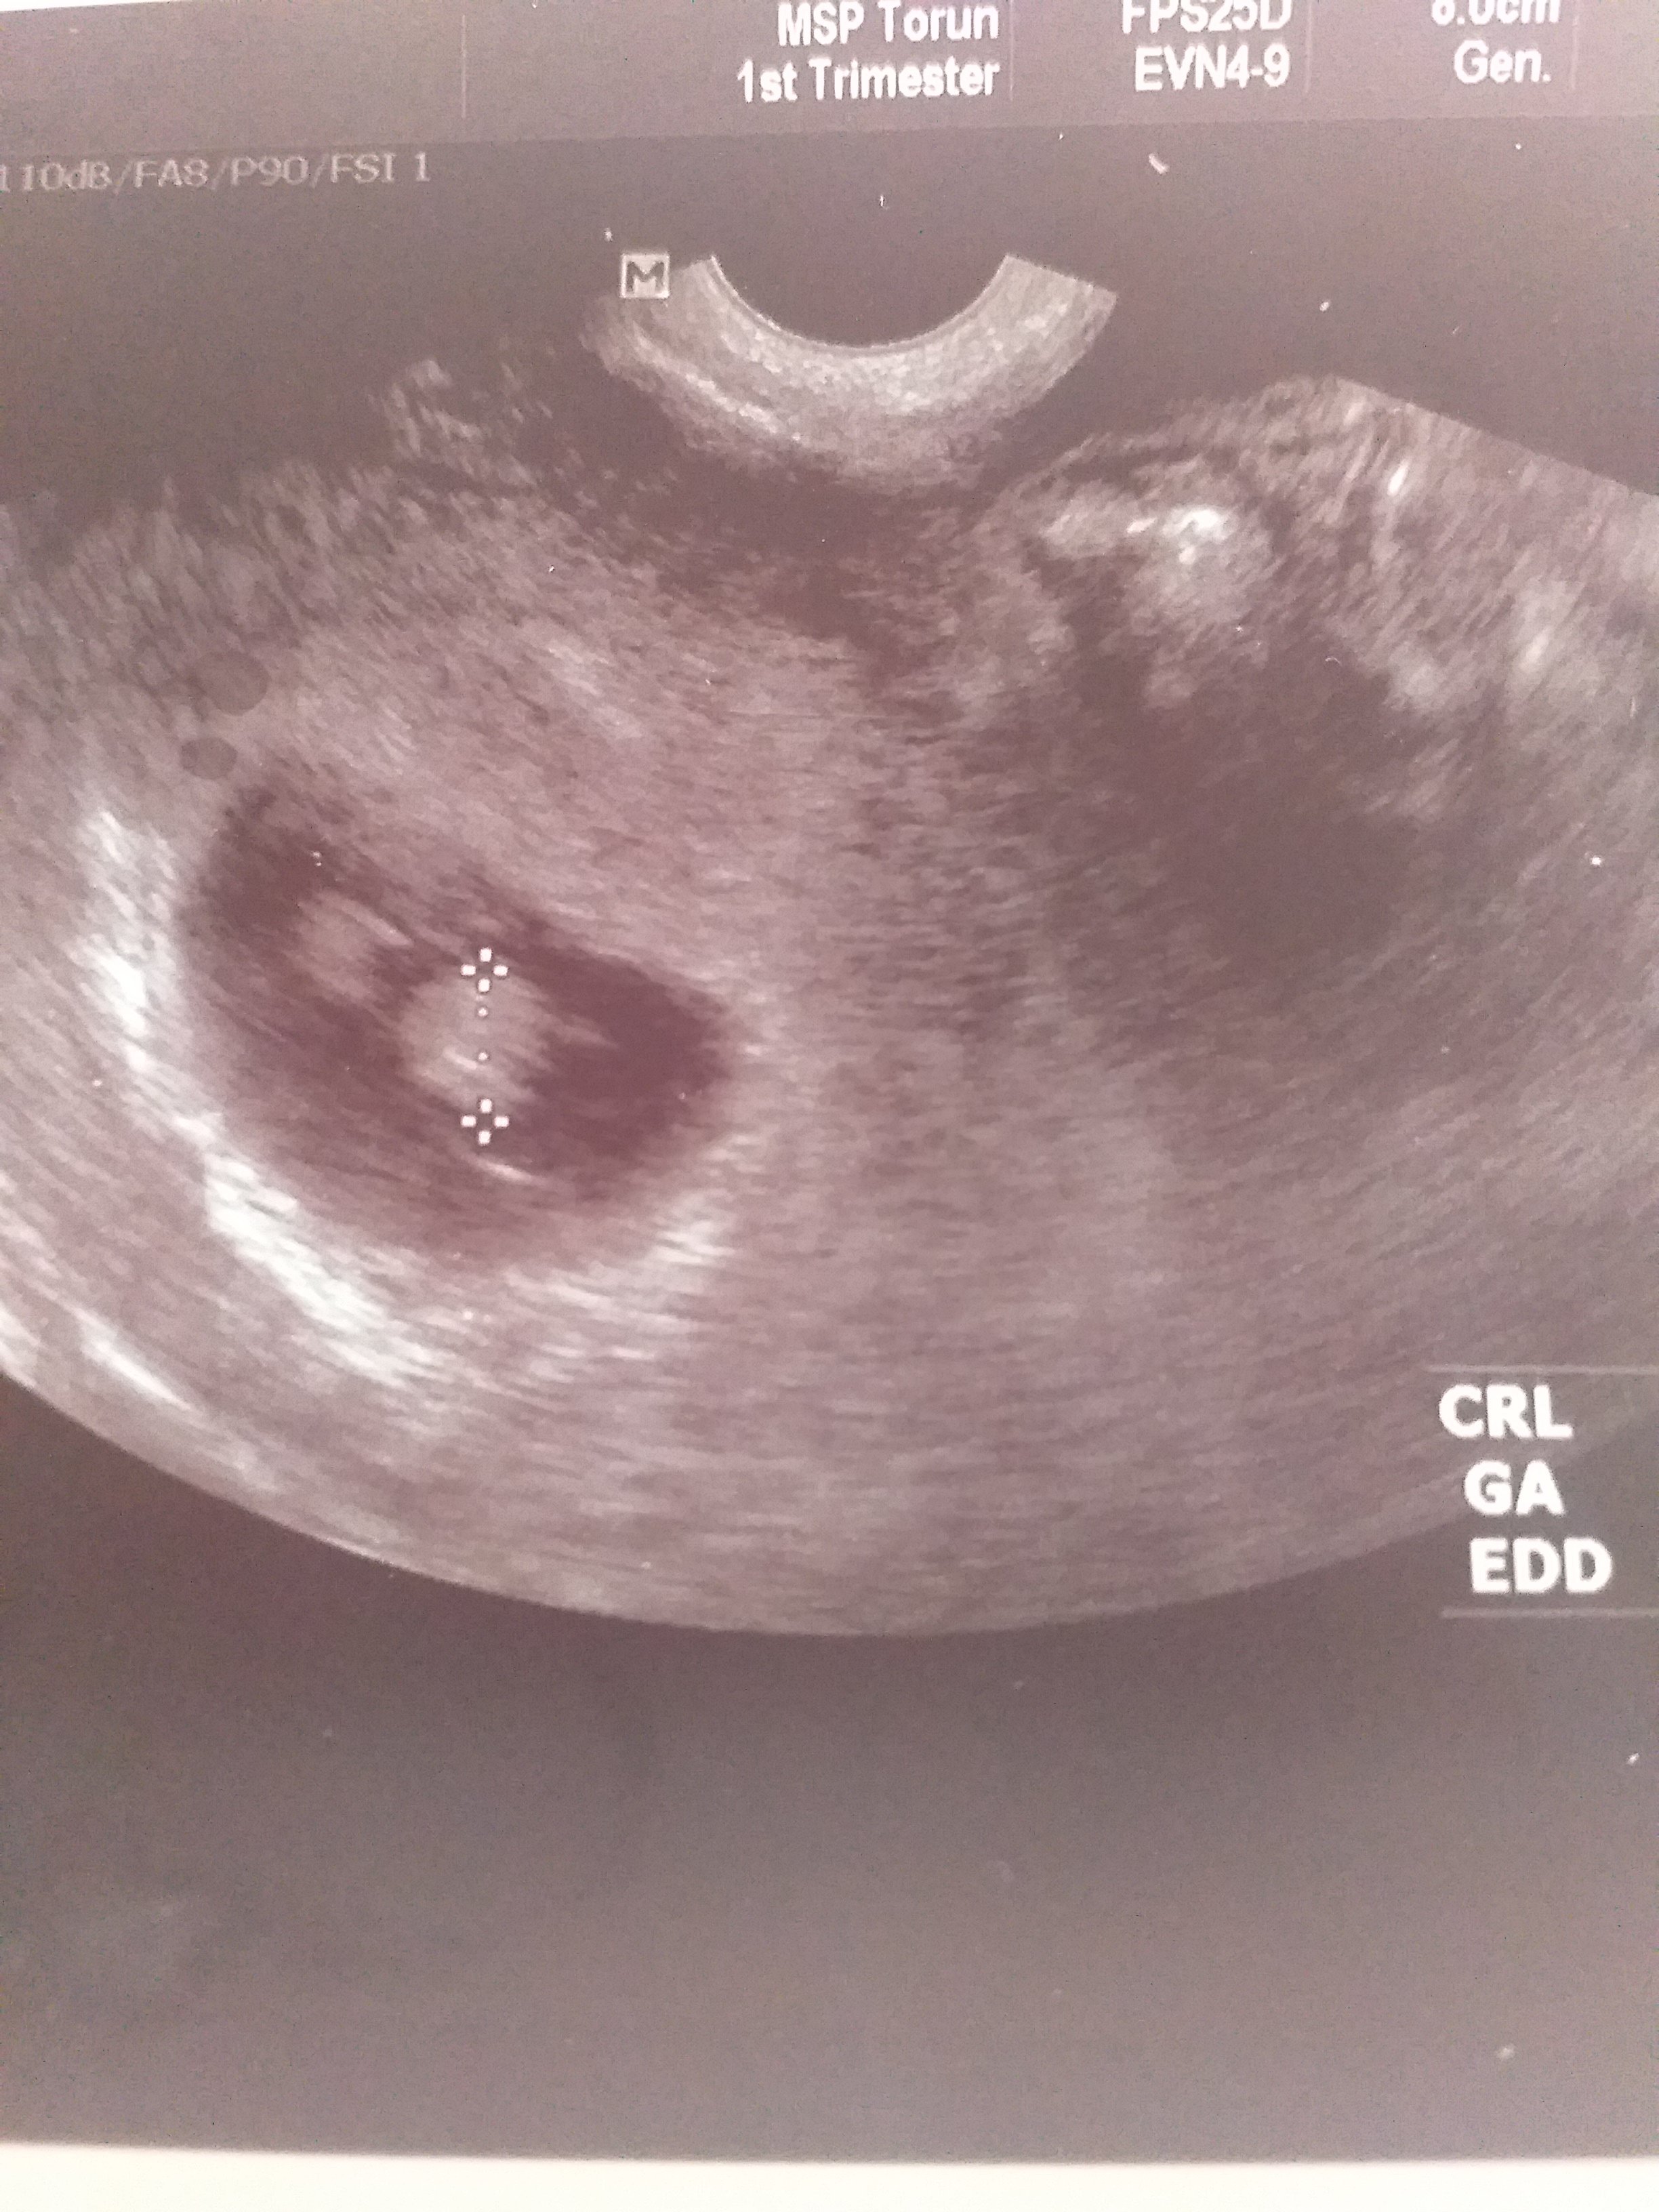

Mam pytanie najlepiej do mam bliźniąt, na zdjęciu usg widać jakby drugi płód. Jednak lekarz wpisał ciąża pojedyncza, zdjęcie usg z 7tygodnia +6dni. Dodam, że to moja druga ciąża lecz w czasie pandemii poszłam do pani ginekolog, która akurat miała termin i to co robiła było jakby z przymusu. Przechodząc do sedna, czy "to coś " widoczne w prawym górnym rogu to drugi płód? Jeśli nie to co to może być?